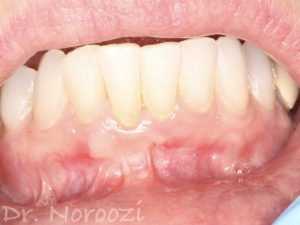

Full Mouth Reconstruction with Fixed Implant Bridge – All on X

All on X implant Full Mouth Implant Reconstruction All on 4 Implants IMPrESS Perio Implant Center Vancouver Burnaby Periodontist Prosthodontist Implant Specialist Dr. Noroozi Periodontist Implant Specialist